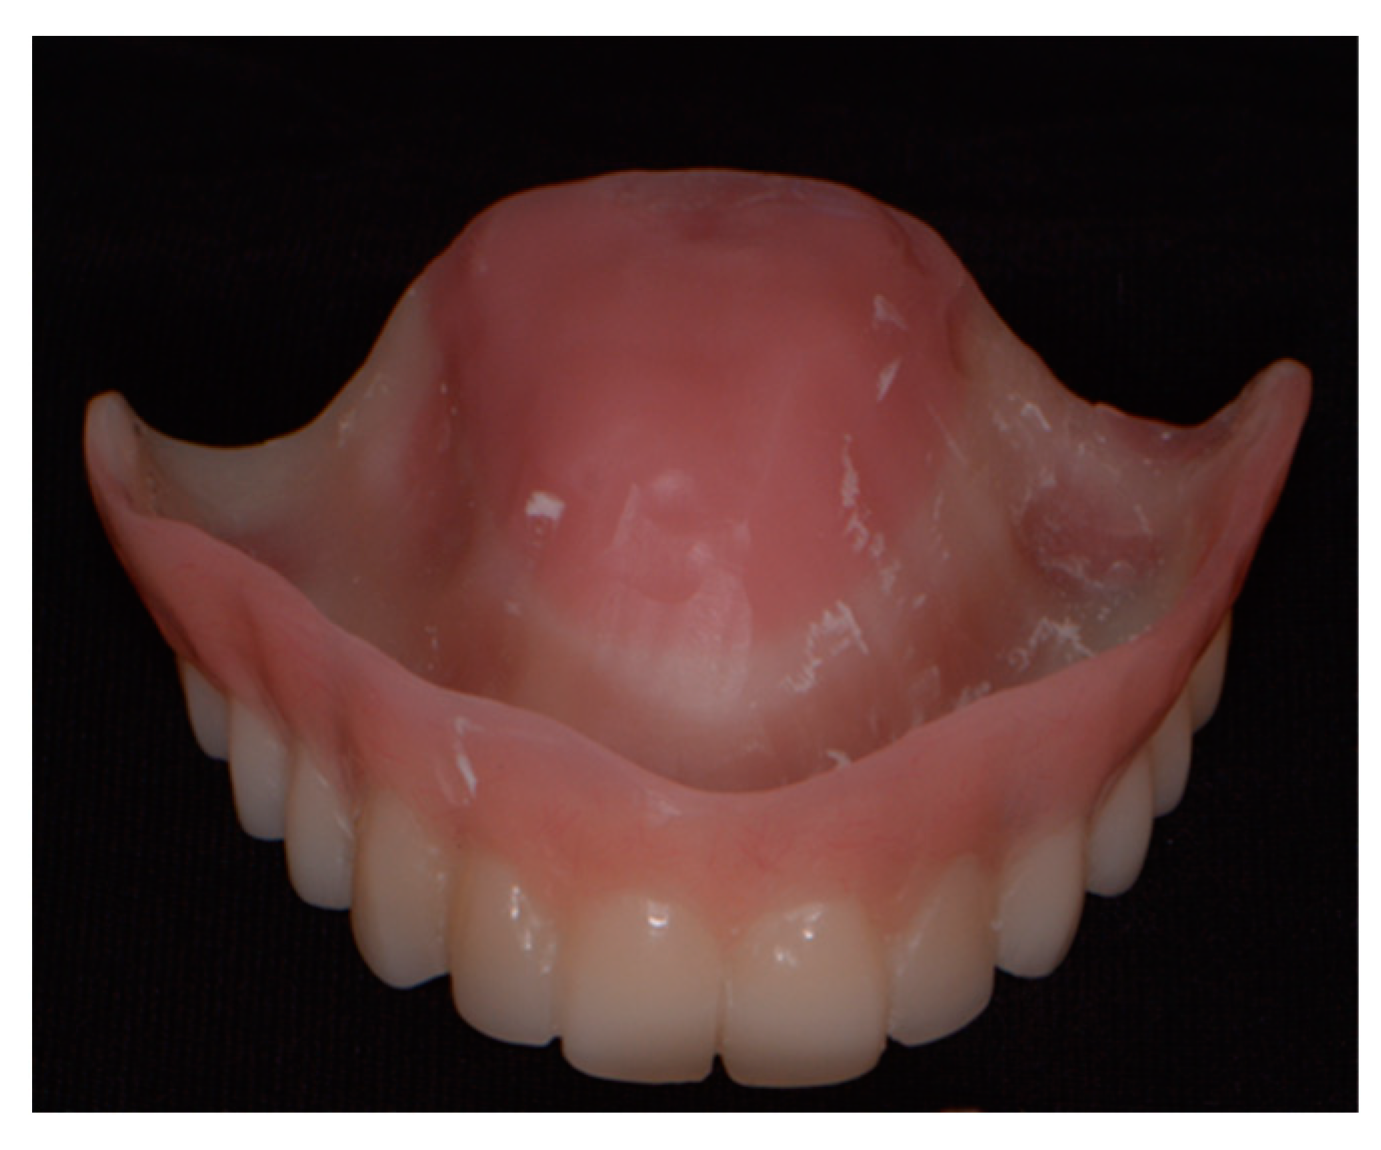

2.2.8. Final Prosthesis

2.3. Follow-Up